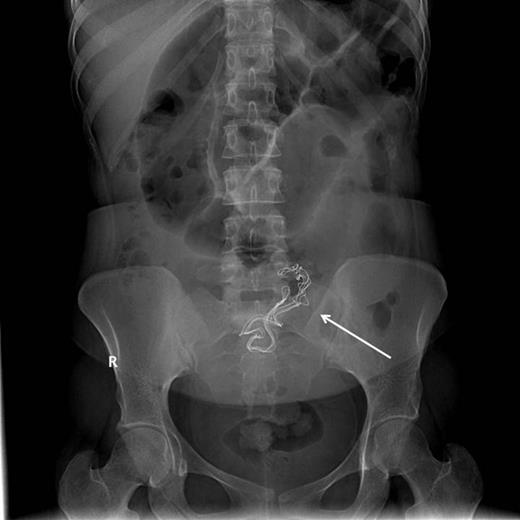

29-year-old woman was referred by her gynecologist with a history of diffuse colicky abdominal pain, nausea, repeated vomiting, constipation and progressive abdominal distention for 7 days prior to hospitalization. She had undergone an emergency cesarean section 9 months previously at a private hospital and since that time she had been complaining of recurrent attacks of nonspecific abdominal pain and occasional episodes of vomiting especially after heavy meals from which she had lost 10 kg since delivery. The patient had attended emergency departments at different institutions with similar complaints and had been discharged home after each occassion, but her symptoms passed undiagnosed. Five days prior to admission, abdominal roentography was done at an emergency department for her abdominal complaint, which showed radio-opaque density in the pelvis (Fig. 1), but it was mistakenly overlooked and she was discharged home with a diagnosis of nonspecific abdominal pain.

Proximal small intestinal dilatation with the radio-opaque mark migrated proximally to the abdomen (arrow), indicating its mobile nature.